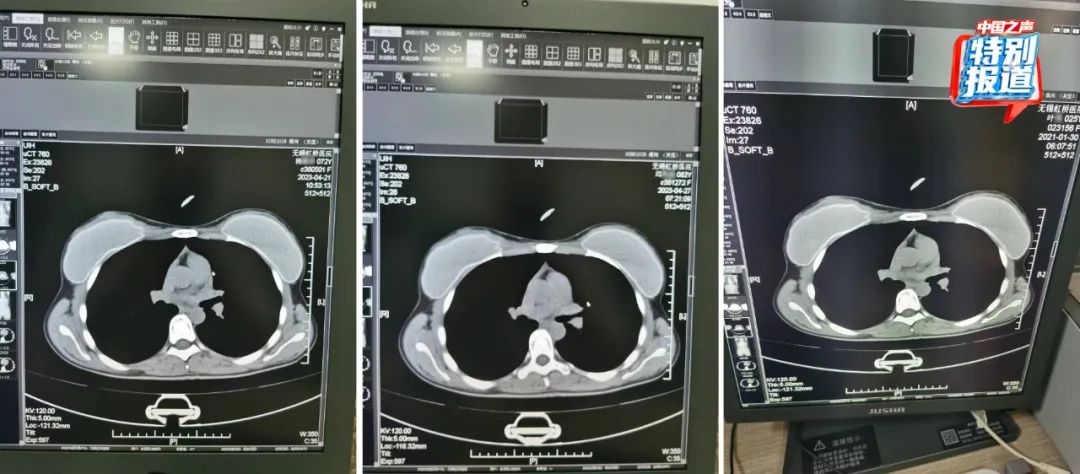

在被举报的病历中,杨某某(72岁)和邱某某(62岁)的病历里,有根据所拍片子的情况做出的诊断,却找不到对应的影像。6月份又查到了她们的CT影像,按照系统记录,这两人都是2023年4月做的胸部CT,片子上能清晰看出,两位患者的吊坠形状、大小和位置都基本一致。

不仅这两位上了年纪的患者CT影像类似,朱成刚比对发现,2021年在他们科做过CT的25岁女性叶某的片子上,也有看起来极为相似的吊坠,肉眼看,三人的片子几乎一模一样。

△72岁的杨某某、62岁的邱某某与25岁的叶某,三人的片子几乎一模一样。 类似这样看上去雷同程度很高的片子,还有不少。系统显示: